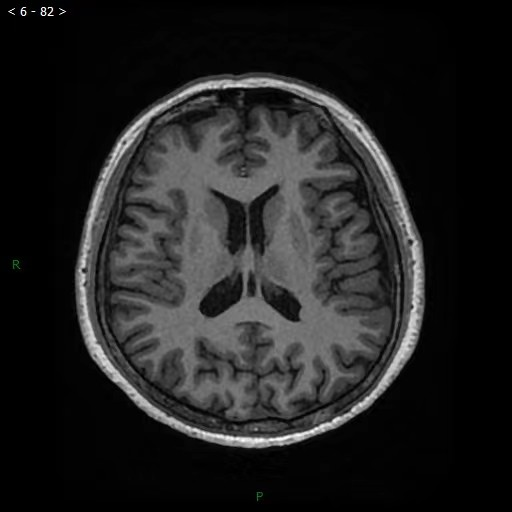

它的成像系统提供了十种自由调节临床对比度,在媲美传统磁共振成像信噪比的同时更利于微小病灶的检出和筛查。其中,相位敏感对比度对于多发硬化有着更高的检出率,灰白质成像对于儿童先天性灰白质异位等疾病具有更优越的显示效果。这些都有助于更早地发现疾病,精确诊断疾病。

图为颅脑3D T1 MP-RAGE成像。